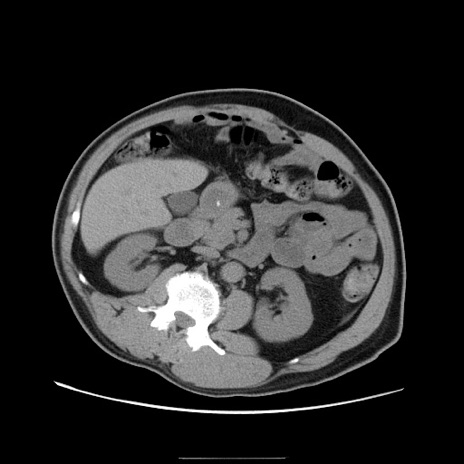

症例22(横断像)

【症例】50歳代男性

【主訴】腹痛

【現病歴】AVMからの被殻出血のため回復期リハ病棟入院中。 本日午後3時頃急に下腹部痛が出現した。

【既往歴】AVM、被殻出血、虫垂炎、高血圧

【身体所見】意識晴明、左半身不全麻痺、会話の理解は良好、36.5°C、腹部:膨隆、全体に板状硬、下腹部正中に圧痛点あり、反跳痛-、筋性防御不明、右下腹部にope scar

【データ】WBC 9400、CRP 0.06